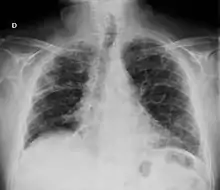

- Pulmón

- La fibrosis pulmonar es una complicación reconocida de la artritis reumatoide[56][57][58] y también puede ser una consecuencia de algunos tratamientos —por ejemplo del metotrexate y leflunomida—.[59] El síndrome de Caplan describe la presencia de nódulos reumatoideos pulmonares en pacientes con artritis reumatoide y exposición al polvo de sílice o carbón. Los derrames pleurales no son raros en el contexto de la artritis reumatoide y obligan a descartar otras posibles causas. Estas alteraciones pulmonares, además de la bronquiolitis obliterante se denominan globalmente enfermedad pulmonar reumatoide, estimándose que al menos una cuarta parte de los pacientes con artritis reumatoide desarrollan afectación pulmonar.[60][61]